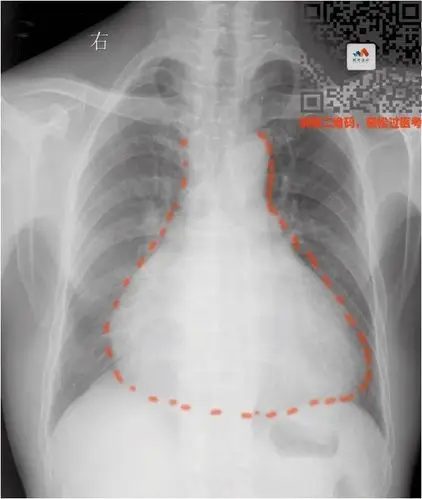

烧瓶心:患者站立位时,由于重力作用积液主要聚集在下方,从而形成烧瓶

要么是心脏本身增大(心包积液—烧瓶心)要么是心包里面灌了水普大型

烧瓶心我的妈呀第一次见这么标准的